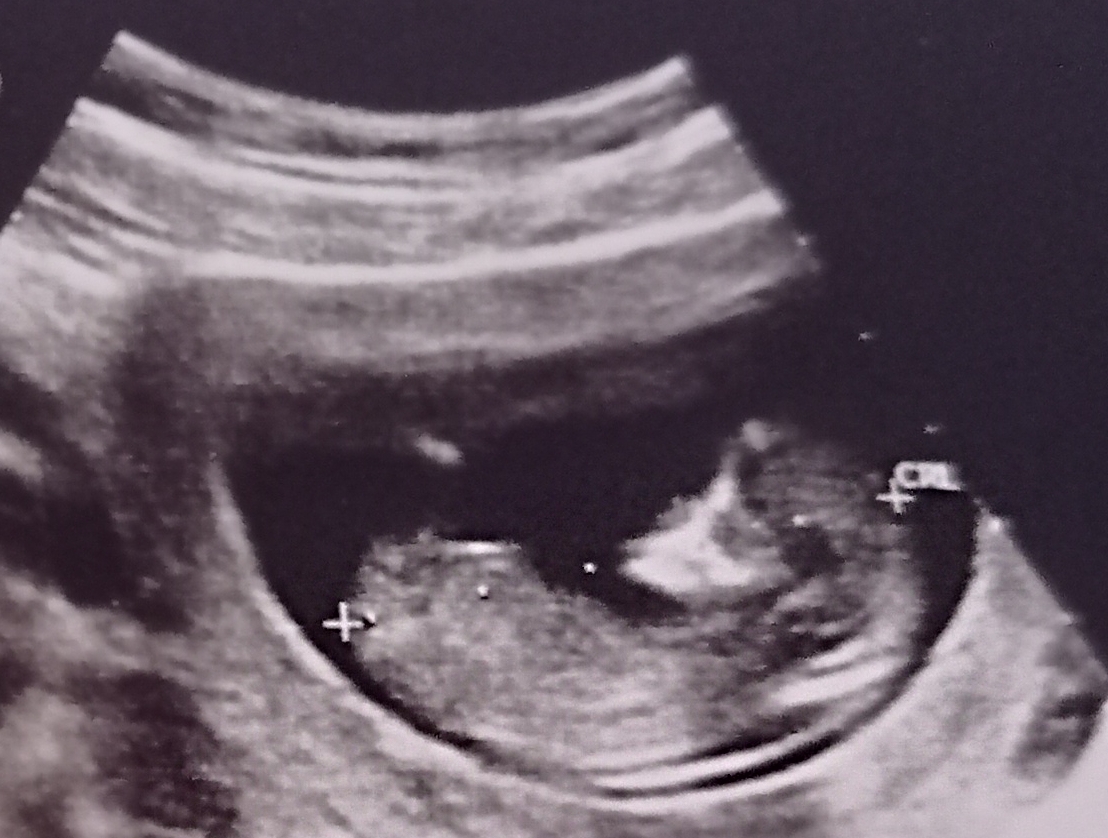

Kızlar 11+6 günlükken bebeğimin ultrason fotoğrafı. Yüzü neden bu şekilde duruyor ve aşağı kısım neden keseye sıfır gözükmüyor bu ense kalınlığı olduğu anlamına mı geliyor 2 li tarama sonuçlarım hala çıkmadı merak içindeyim

ense kalınlığı var gibi geldi dedi, bpd değerini olcmus ama 8 mm çıkmış

Bpd değerini olctu 8 mm çıktı bu normal midir peki bilgin var mı

Bebeğinizi kız sanırım. Allah korktuğunuz yere uğratmasın inşallah brnimde kızımda down sendrom riski yüksek çıkmıştı şükür sağlıklı dünyaya geldi